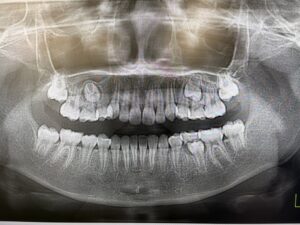

プレオルソで機能矯正を致しました。

熱心に毎晩装着してくれたおかげで、1年半ほど経った様子は、こちらです。

あと少し乳歯が残っていますが、綺麗な歯並びになりますね。